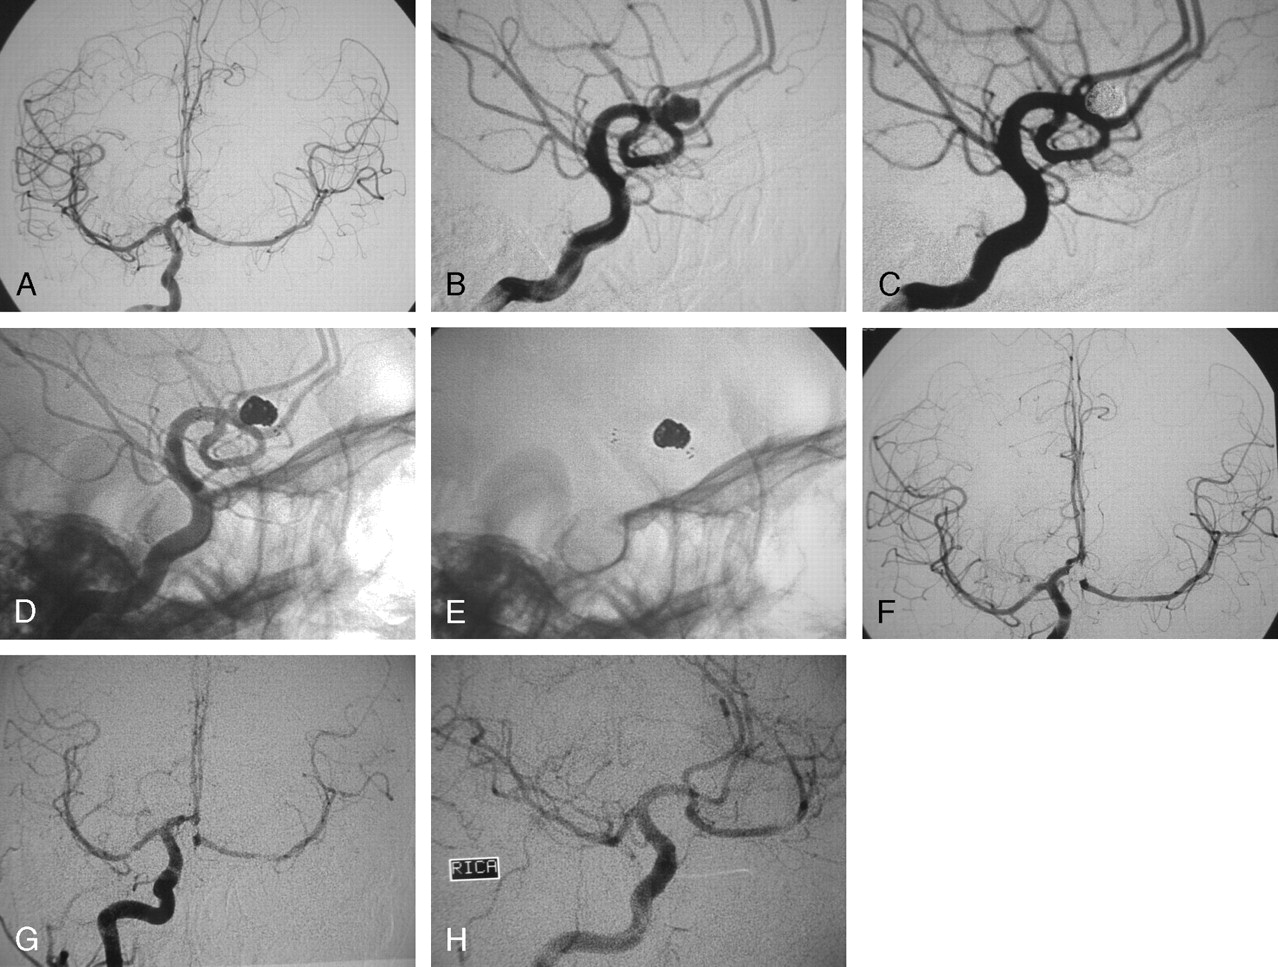

Хирургические процессы при эмболизации гемангиомы на фото

Раздел: Снимки-откровения